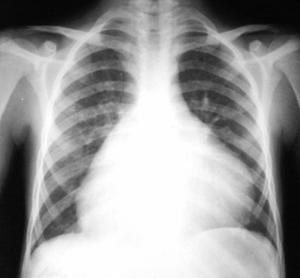

Radiologice (de obicei nerelevante, dependente de cantitatea de lichid din pericard).

Imagine Rx de pericardita acuta

Semne radiologice cardiopulmonare:

cardiomegalie importanta cu contururi net trasate, stergerea arcuatiei normale, cord 'in carafa',

circulatie pulmonara normala.

radiologic: cord de dimensiuni normale cu contur net trasat, eventual cu calcificari pericardice si circulatie pulmonara normala,